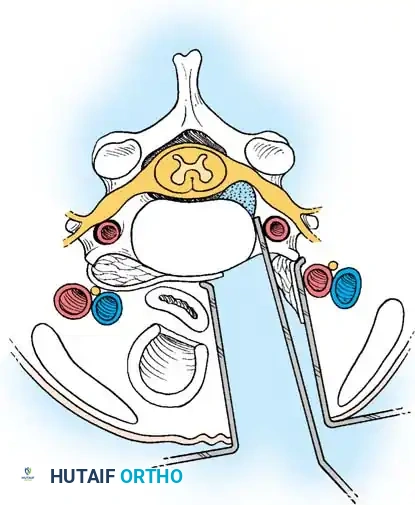

Step 4: Endplate Preparation and Fusion

The cartilaginous endplates are meticulously decorticated using a curette or burr to expose bleeding subchondral bone, which is critical for arthrodesis. Care must be taken not to breach the structural integrity of the endplate to prevent graft subsidence.

An appropriately sized structural allograft, autograft, or synthetic cage packed with osteoinductive material is impacted into the disc space under gentle cervical traction. An anterior cervical plate is then secured with screws into the adjacent vertebral bodies to provide immediate biomechanical stability.